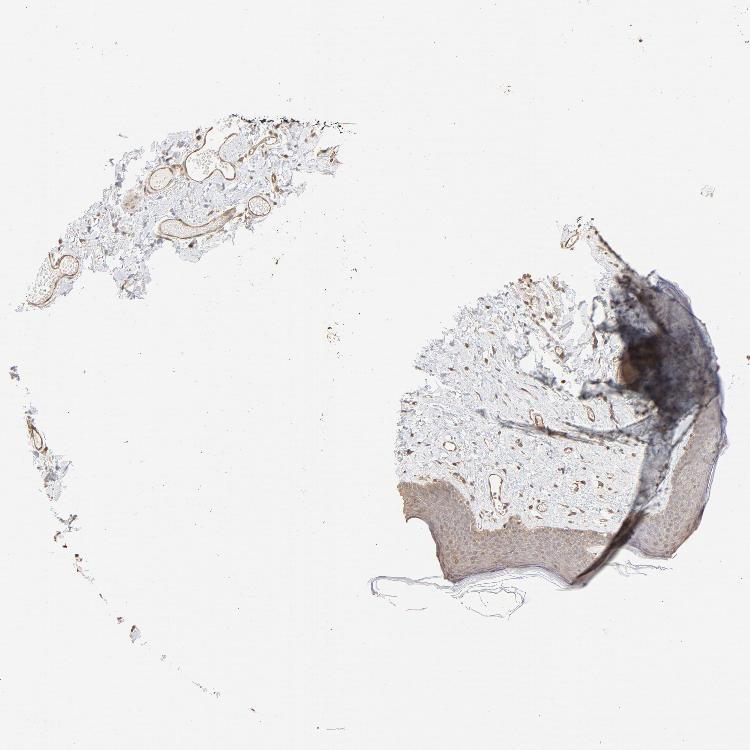

SKIN 1 - Antibody stainingi

Antibody staining in the annotated cell types in the current human tissue is reported as not detected, low, medium, or high, based on conventional immunohistochemistry profiling in selected tissues. This score is based on the combination of the staining intensity and fraction of stained cells.

Each image is clickable and will lead to virtual microscopy that enables deeper exploration of all samples and also displays staining intensity scores, fraction scores and subcellular localization as well as patient and tissue information for each sample.

Antibody HPA043236Antibody CAB003848

Langerhans LowMedium

Fibroblasts LowMedium

Keratinocytes MediumMedium